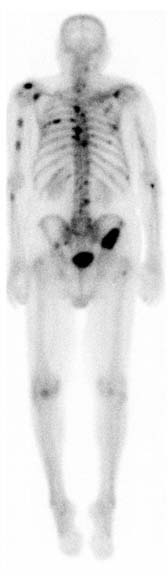

Scintigrafia scheletrica whole-body normale.